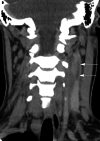

Lemierre's syndrome is a condition characterized by septicemia, with bacteremia, thrombophlebitis of the internal jugular vein (IJV), and septic embolization to distant organs following a recent upper respiratory infection (URI). Fusobacterium necrophorum, an anaerobic Gram-negative rod, has been mostly implicated as the causative organism of this condition that tends to affect healthy teenagers and young adults. While once regarded as a disease of old, it has seen a resurgence in recent times, possibly due to antibiotic stewardship and current trends of reduced antibiotic use for URIs. It is important that the modern physician has a high index of suspicion, as well as the characteristic presentation of this potentially fatal illness. Current treatment guidelines are centered on the use of appropriate antibiotics, drainage of purulent collections when possible, and, in some situations, anticoagulants have been utilized. This study describes a case of a young lady who presented with symptoms of chest pain and deteriorating oxygen saturations following recent treatment for acute tonsillitis.